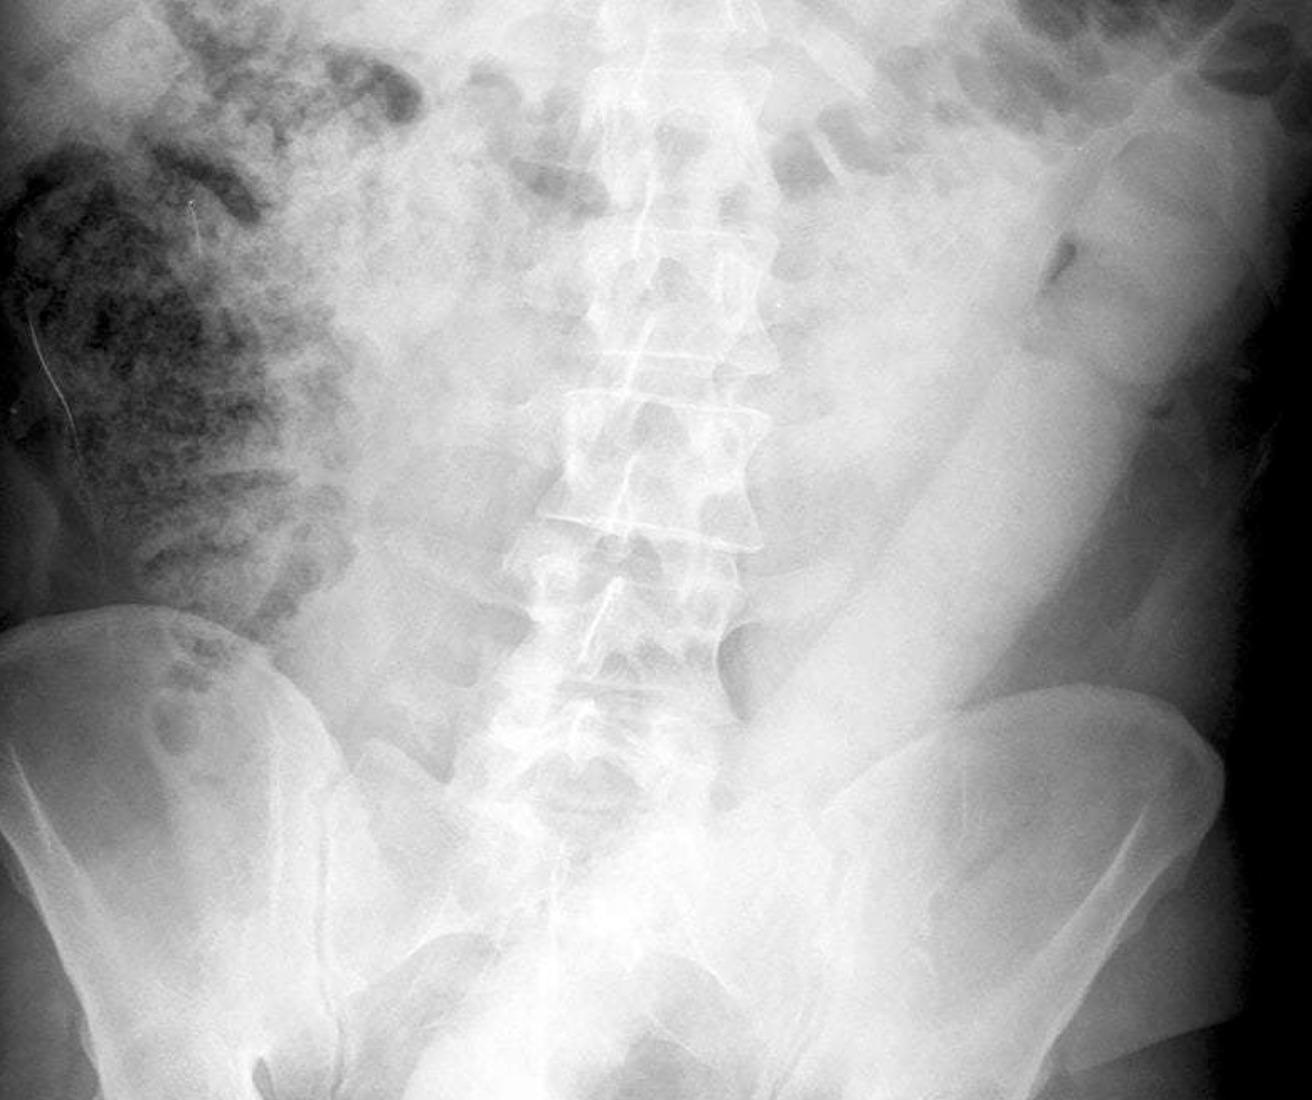

Les meurs et les mentalités se sont libérés depuis. Godmichet, fruits, légumes, téléphones… les médecins doivent redoubler d’inventivité pour retirer les objets restés bloqués dans le rectum de leurs patients. En Italie, le Dr. Lorenzo Dioscoridi, spécialisé dans l'endoscopie, a ainsi développé un nouvel outil pour faire sortir un godemichet en caoutchouc de 60 centimètres d’un anus (voir la radio ci-dessus).

En se présentant aux urgences, un homme de 31 ans a expliqué à l'équipe médicale qu'il n'était pas parvenu à le retirer par lui-même. Dans cette situation depuis 24 heures, le patient se sentait bien, ne ressentant qu’une légère douleur.

Pour éviter de le faire passer sur le billard, l’équipe de Lorenzo Dioscoridi a d’abord tenté de retirer l’énorme objet avec des méthodes existantes, sans succès. Les soignants ont alors eu l’idée de réaliser une espèce de lasso, assez rigide pour attraper le sex-toy (voir la photo ci-dessous). Un fil médical poussé dans un stent colorectal a finalement fait l’affaire, et le patient a pu rentrer chez lui le jour même, sans plus de complications. Les médecins estiment que cette nouvelle technique devrait être pérennisée pour prendre en charge les objets particulièrement volumineux.